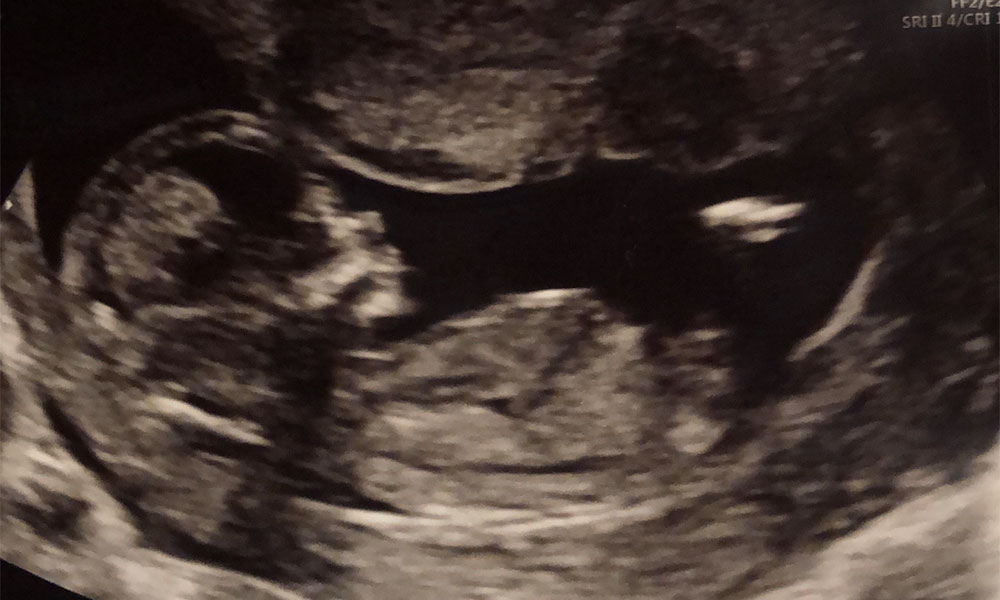

The couple’s 12 week baby scan. (Ross Muller)